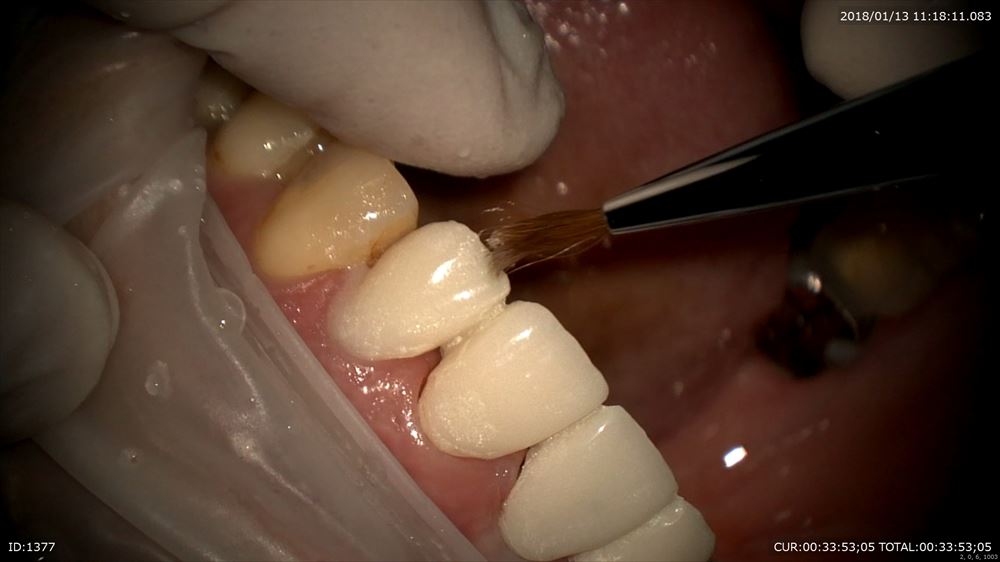

右上1番のインプラント歯茎の形態を仮歯で作ります。

マイクロスコープ治療で仮歯を調整。

エマージェンスプロファイルを調整。

仮歯完成!!インプラントの淵が見えなくなりました。あー緊張した。ここまで1年。患者さま喜んで頂けました。